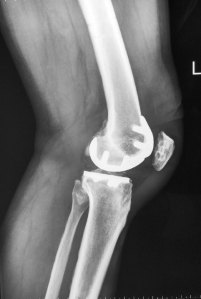

X-rays showed mild narrowing of the medial compartment of his left knee. In addition, there was an obvious severe osteoarthritis of the patellofemoral joint (kneecap joint).

Post-operative check x-rays showed excellent alignment of the implants.